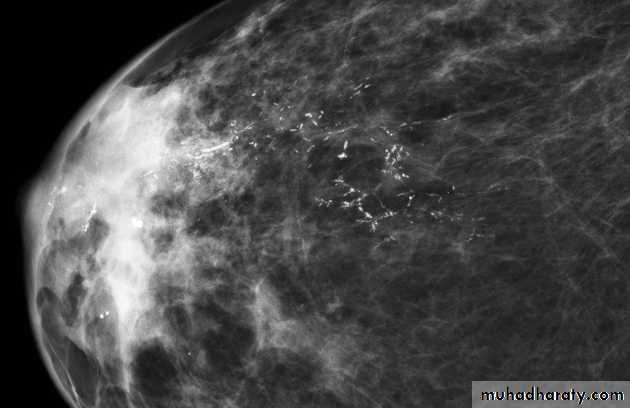

Micro calcifications

Micro calcifications are tiny specks of calcium in the breast. Micro calcifications seen on a mammogram are of more concern than macrocalcifications, but they do not always mean that cancer is present. The shape and layout of microcalcifications help the radiologist judge how likely it is that cancer is present.

In most cases, the presence of microcalcifications does not mean a biopsy is needed. But if the microcalcifications have a suspicious look and pattern, a biopsy will be recommended. (During a biopsy, the doctor removes a small piece of the suspicious area to be looked at under a microscope. A biopsy is the only way to tell if cancer is really present.)